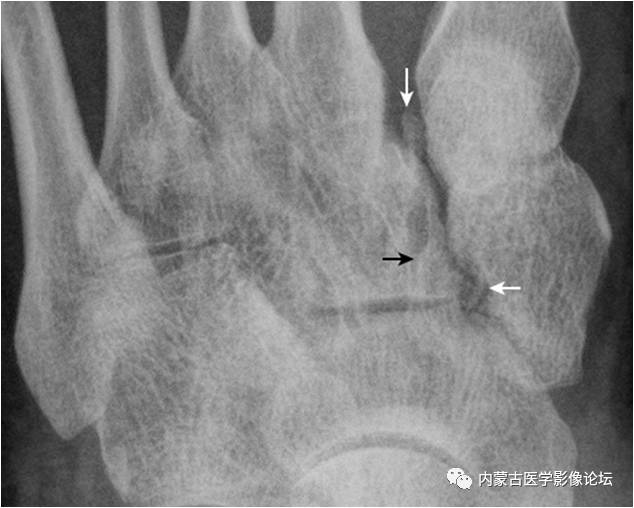

16.第5跖骨粗隆骨化中心:第5跖骨粗隆骨化中心(箭),形态多样,A(女,10岁)为线样且不连续,B(男,13岁)为多发(箭与箭头),C(男,12岁)为边缘光整,D(男,11岁)为内缘粗糙伴裂隙。需与撕脱骨折鉴别,其与粗隆长轴近似平行,而撕脱骨折为腓骨短肌肌腱牵拉所致,骨折线多为横行。